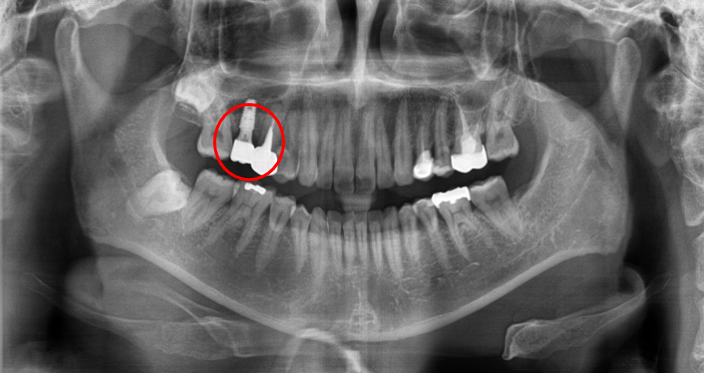

임플란트 치료 전&후

(좌)2021-07-22 / (우) 2021-11-01

임플란트 치료 BEFORE & AFTER입니다. 비어있는 공간에 치아가 알맞게 식립된 것을 알 수 있습니다.